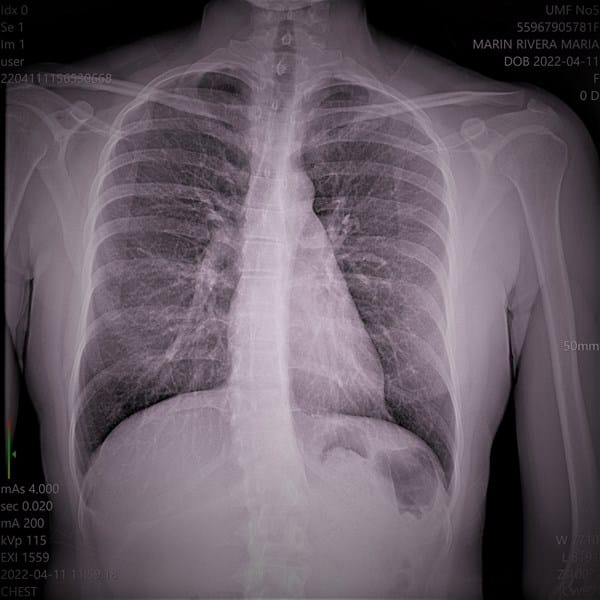

Formación ProfesionalUniversidadesMódulos Formativos carmen velasco el 22 sep. 22 De cuantos grados es la angulación Estas son radiografías de mi escoliosis De cuantos grados es la angulación de mi escoliosis necesito saber Seguir Siguiendo Dejar de seguir